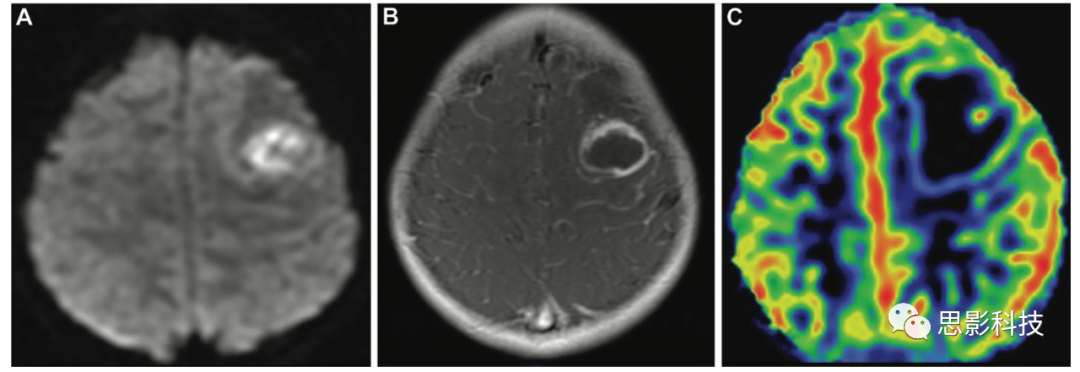

治療反應(yīng)評(píng)估 高級(jí)別膠質(zhì)瘤的治療反應(yīng)評(píng)估是一個(gè)主要的挑戰(zhàn),特別是在區(qū)分在有新的或Gd強(qiáng)化增加的患者中,放射引起的壞死和復(fù)發(fā)的腫瘤。ASL有助于區(qū)分有新的或Gd強(qiáng)化增加的情況,因?yàn)榉派湫詨乃劳ǔ1憩F(xiàn)為低CBF,而大多數(shù)復(fù)發(fā)腫瘤表現(xiàn)為高CBF(15、16)。據(jù)報(bào)道,ASL MRI在區(qū)分腫瘤復(fù)發(fā)和放射性壞死方面具有與DSC MRIPET相似的診斷性能,在高級(jí)別膠質(zhì)瘤中可能更準(zhǔn)確,特別是存在混合放射性壞死區(qū)域(敏感度為94%)DSC MRI受血腦屏障破壞的T1T2效應(yīng)和易感性偽影的影響,而這些因素對(duì)ASL影響較小。

15 一例59歲男性因肺癌中樞神經(jīng)系統(tǒng)轉(zhuǎn)移而接受放射治療后發(fā)生放射性壞死。(A)軸位增強(qiáng)的T1加權(quán)像顯示邊緣不均勻強(qiáng)化,左側(cè)中央旁小葉有不規(guī)則病變(箭頭),磁敏感加權(quán)成像顯示周圍有廣泛的血管性水腫(未顯示)。(B)ASL MRI顯示受影響區(qū)域腦血流量降低,提示放射性壞死。

16 一例53歲女性在晚期高級(jí)別膠質(zhì)瘤術(shù)后影像隨訪時(shí)殘留或復(fù)發(fā)腫瘤。(A,B)軸位彌散加權(quán)(A)和高空間分辨率增強(qiáng)T1加權(quán)(B)顯示不均勻強(qiáng)化和沿手術(shù)腔后緣的受限擴(kuò)散(箭頭),沿后內(nèi)側(cè)邊緣有結(jié)節(jié)狀和不規(guī)則的局灶增厚。

(C)ASL MR圖像顯示外科手術(shù)腔后內(nèi)側(cè)緣高CBF,伴有局灶結(jié)節(jié)增厚(箭頭),表明存在復(fù)發(fā)或殘留腫瘤。